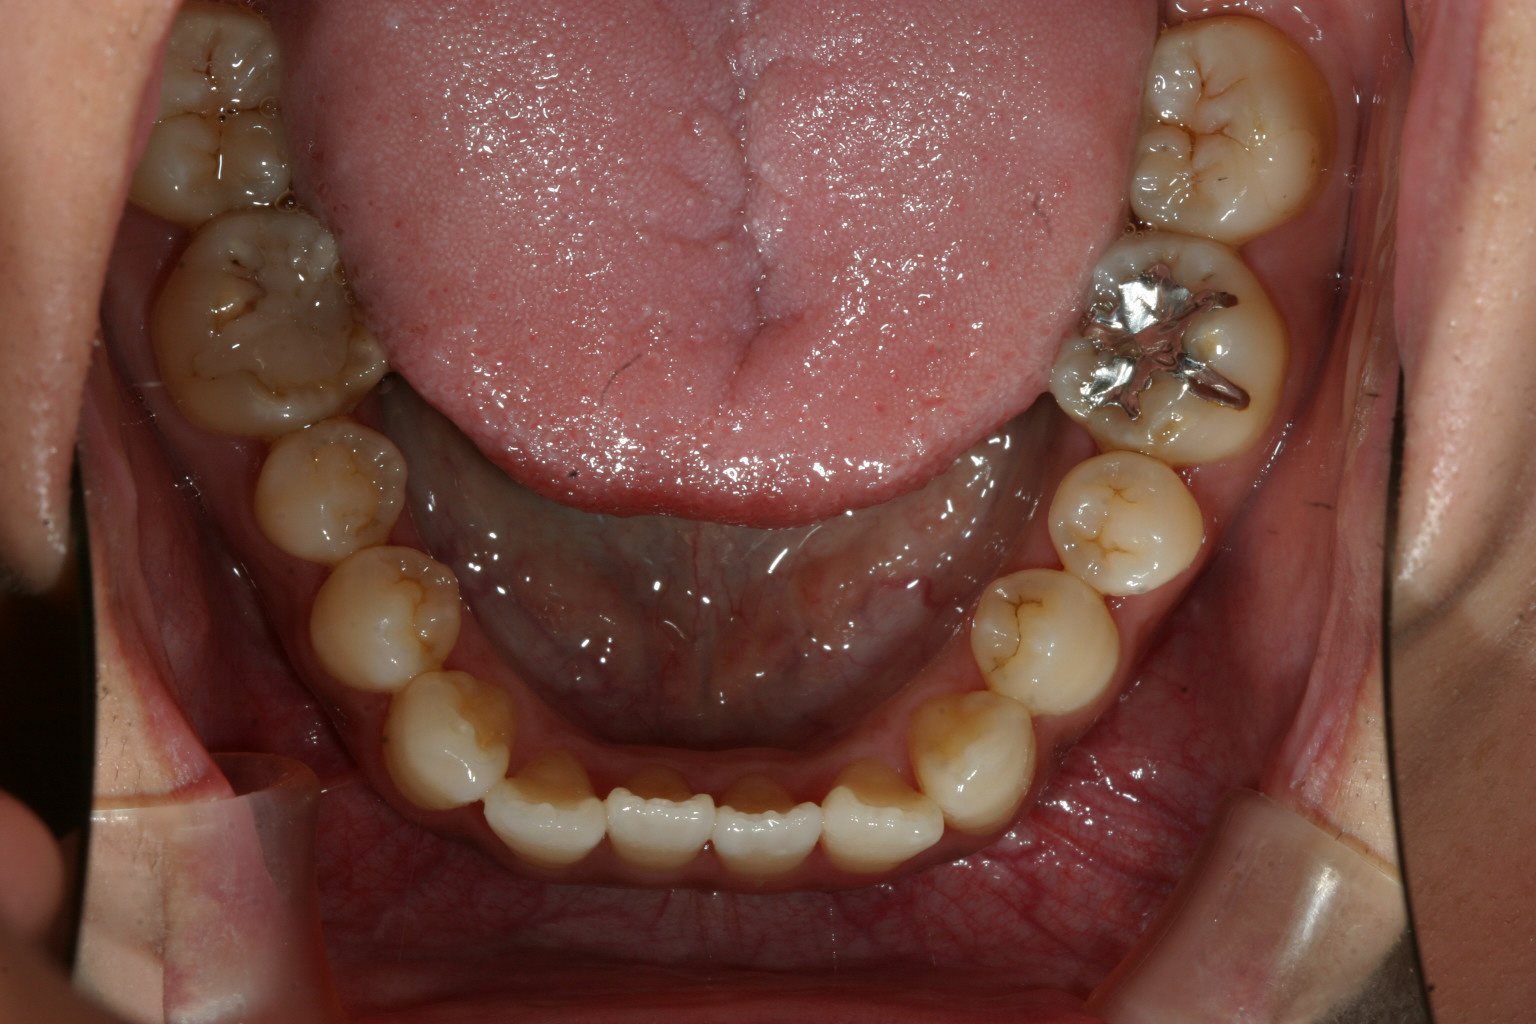

下顎の症状は軽度ですね~

横から見た出っ歯感は前から見た感じより大した事無いですね!